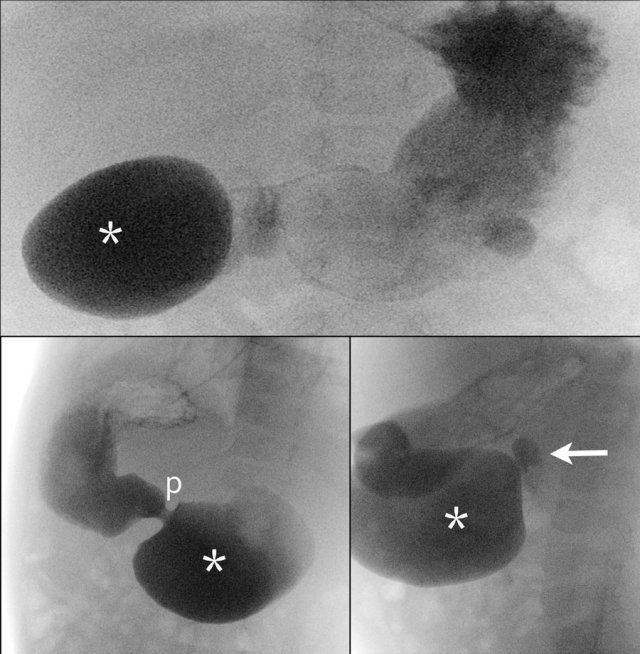

First look at the images of the upper GI-study and describe the findings.

Then continue reading.

The findings are:

- Dilated proximal duodenum (asterix)

- Small amount of contrast passes through the duodenal web to the distal duodenum (arrow)